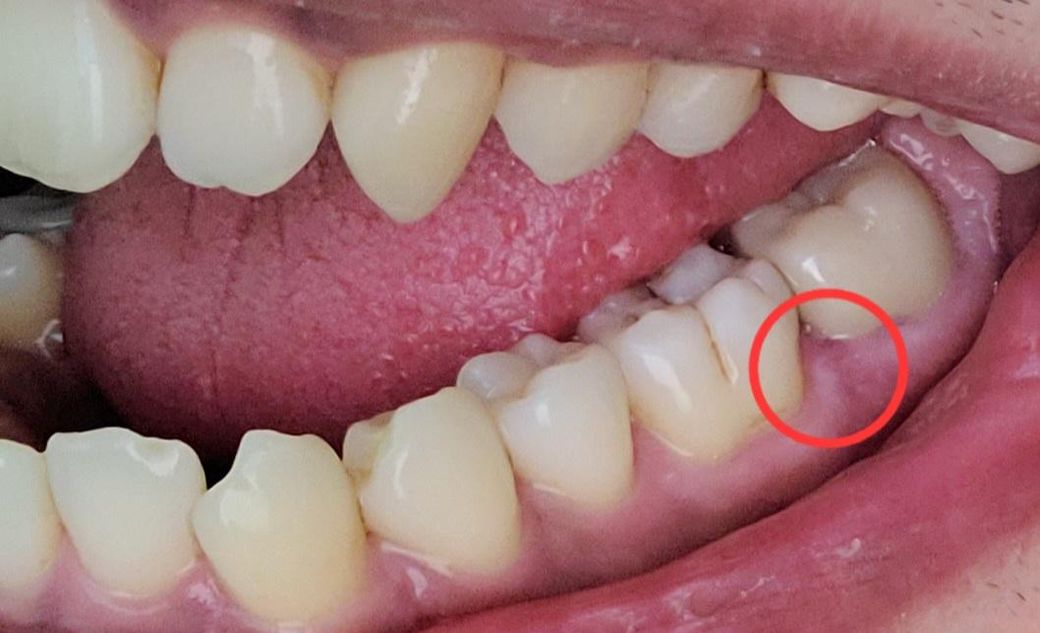

오른쪽 맨끝 어금니 입니다. 10년된 신경치료한 금크라운을 지르코니아로 새로 교체한지 2개월 됬는데요. 저 동그라미친 부분 잇몸이 누르면 아프고 자주 간질거립니다. 물론 저번주에 잇몸치료도 받고왔습니다. 근데 다시그러네요. 받을때만 괜찮습니다. 이러면 크라운경계부 문제인가요? 아니면 뿌리문제일까요. 최근에 찍은 엑스레이도 첨부합니다. 크라운문제라면 A/S가능한지 궁금합니다.

• 2번 째 사진

일단 사진상 보기에 주변 잇몸이 아주 건강한상태는 아닙니다 잇몸치료받고 회복기간일 수도 있습니다

그 앞 치아 충치도 한번 체크해보세요